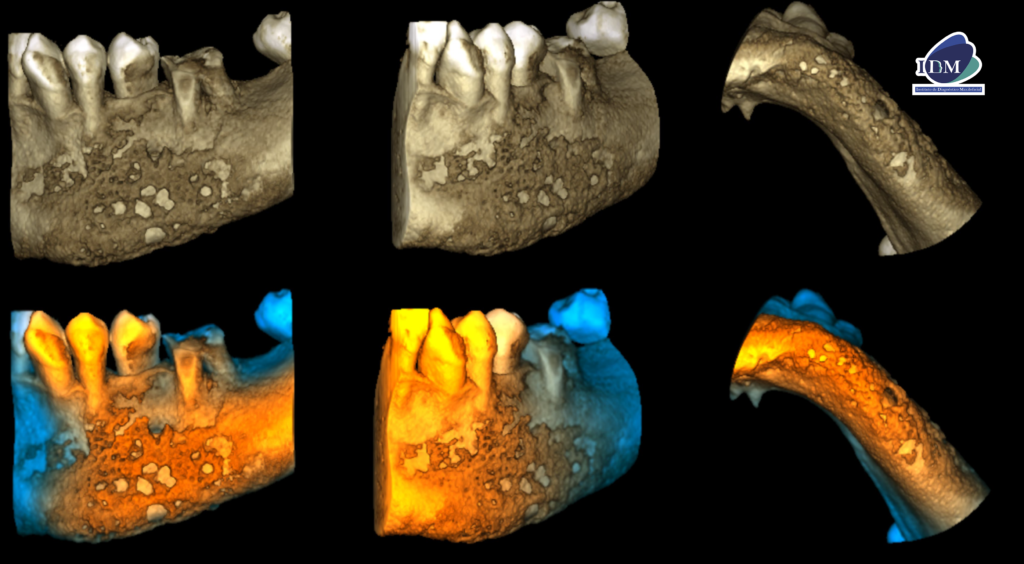

En el estudio complementario mediante tomografía computarizada de haz cónico (TCHC), se confirma la presencia de una reacción ósea perióstica que afecta la tabla ósea vestibular, la basal mandibular y, parcialmente, la tabla ósea lingual en su región caudal (cortes axiales, tangenciales y transaxiales). En las piezas dentarias, se observa una obturación parcial de los conductos y procesos osteolíticos periapicales en la pieza 36 (cortes transaxiales).

RECONSTRUCCIÓN 3D

- Osteomielitis mandibular crónica.